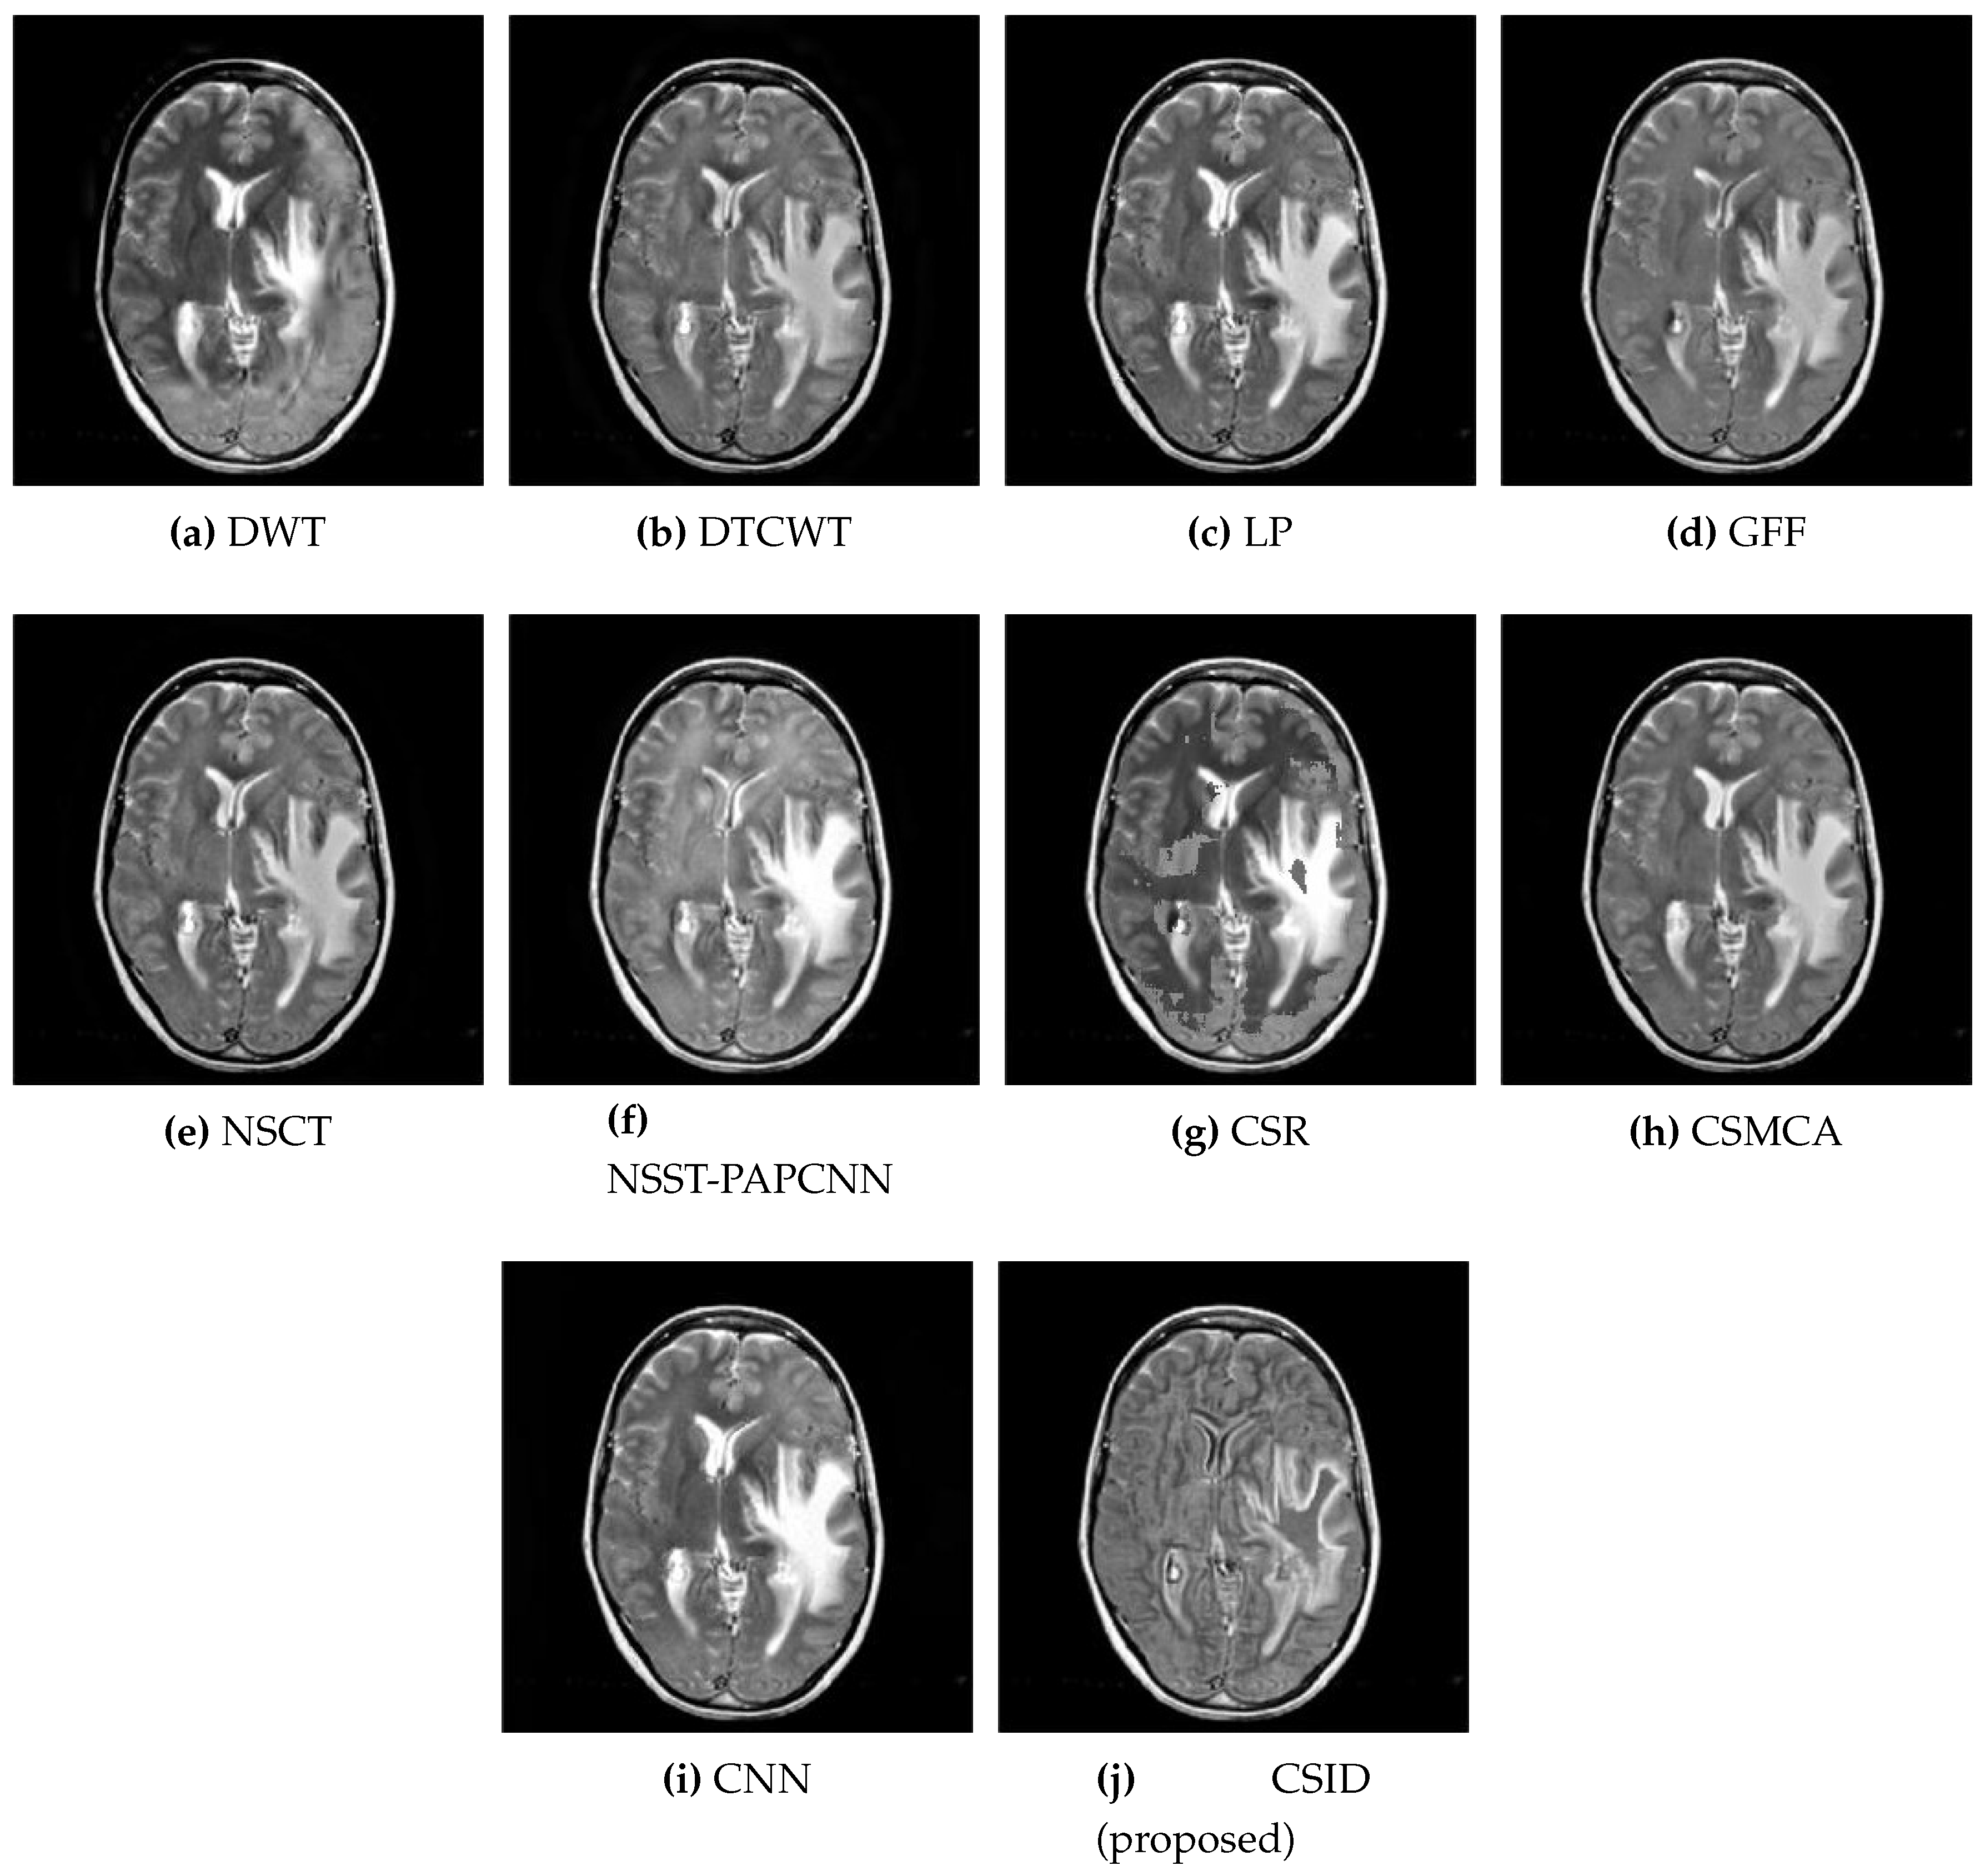

This subsection presents the results based on visual observations of the images generated through our proposed CSID algorithm in comparison with the aforementioned algorithms using different datasets, i.e., Data-1 through Data-6. Visual quality comparison of the Data-1 dataset using different fusion methods, i.e., DWT, DTCWT, LP, GFF, NSCT, NSST-PAPCNN, CSR, CSMCA, CNN, and the proposed algorithm are shown in Figure 5a through Figure 5j, respectively. A CT image gives information about hard tissues and their structures, whereas an MRI image indicates information regarding soft tissues. For better diagnosis, it is essential to merge critical information of the aforementioned images into one fused image [12]. In this regard, the aforementioned set of algorithms perform multimodal image fusion. The qualitative results shown in Figure 5 depict inferior performance, in terms of contrast and visual effect, for DWT (Figure 5a), DTCWT (Figure 5b), NSCT (Figure 5e), and CSR (Figure 5g). Note that these algorithms are not capable of preserving information in the fused image, which relates to the objective evaluation metric MI that remains proportional to the level of information extraction. Additionally, Section 5.2.2 further validates this claim through quantitative analysis, where DWT, DTCWT, NSCT, and CSR exhibit lower MI score in comparison with other algorithms. Moreover, GFF (Figure 5d) and NSST-PAPCNN (Figure 5f), yield better results, when compared with DWT, DTCWT, NSCT, and CSR algorithms, by avoiding information loss. However, the lack of noise removal results in over enhancement of the structural features in these algorithms. CSMCA (Figure 5h) and CNN (Figure 5i) further improve the visual quality, where enhanced visualization remains an outcome of lesser information loss. Finally, our proposed CSID algorithm (Figure 5j) yields clear, high contrast and superior visual quality and preserves the salient features, which include considerably enhanced bone structure and soft tissues information in comparison with other given algorithms.

Figure 5. Comparative analysis, based upon visual observation, of the resultant fused images generated by the given set of algorithms using Data-1 dataset.